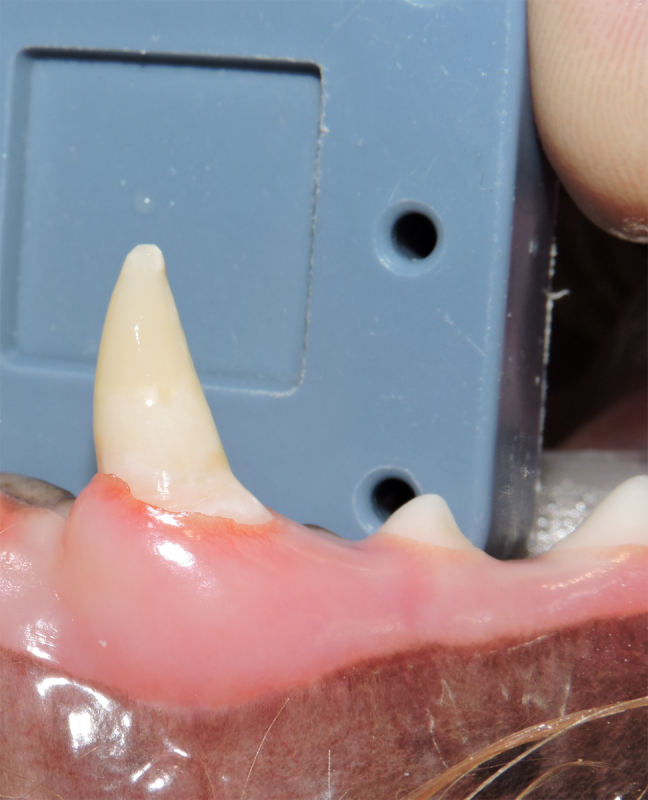

Tooth Resorption

Tooth resorption is a disease process where the body begins to break down the adult tooth. It is widely known to occur in cats but can also occur in dogs. In cats these lesions are thought to be inflammatory, while in dogs they can be more of a replacement resorption process. These lesions can be very painful and should be treated, generally with extraction depending on the type of resorption that is occurring. The disease can be progressive and affect many teeth over several years. It is important to have regular checkups and yearly dental cleanings to monitor for these lesions.